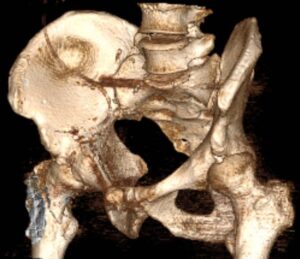

Пояснюємо, які операції доступні для різних анатомічних зон, як плануємо втручання та готуємо пацієнта до відновлення.

Читати далі →